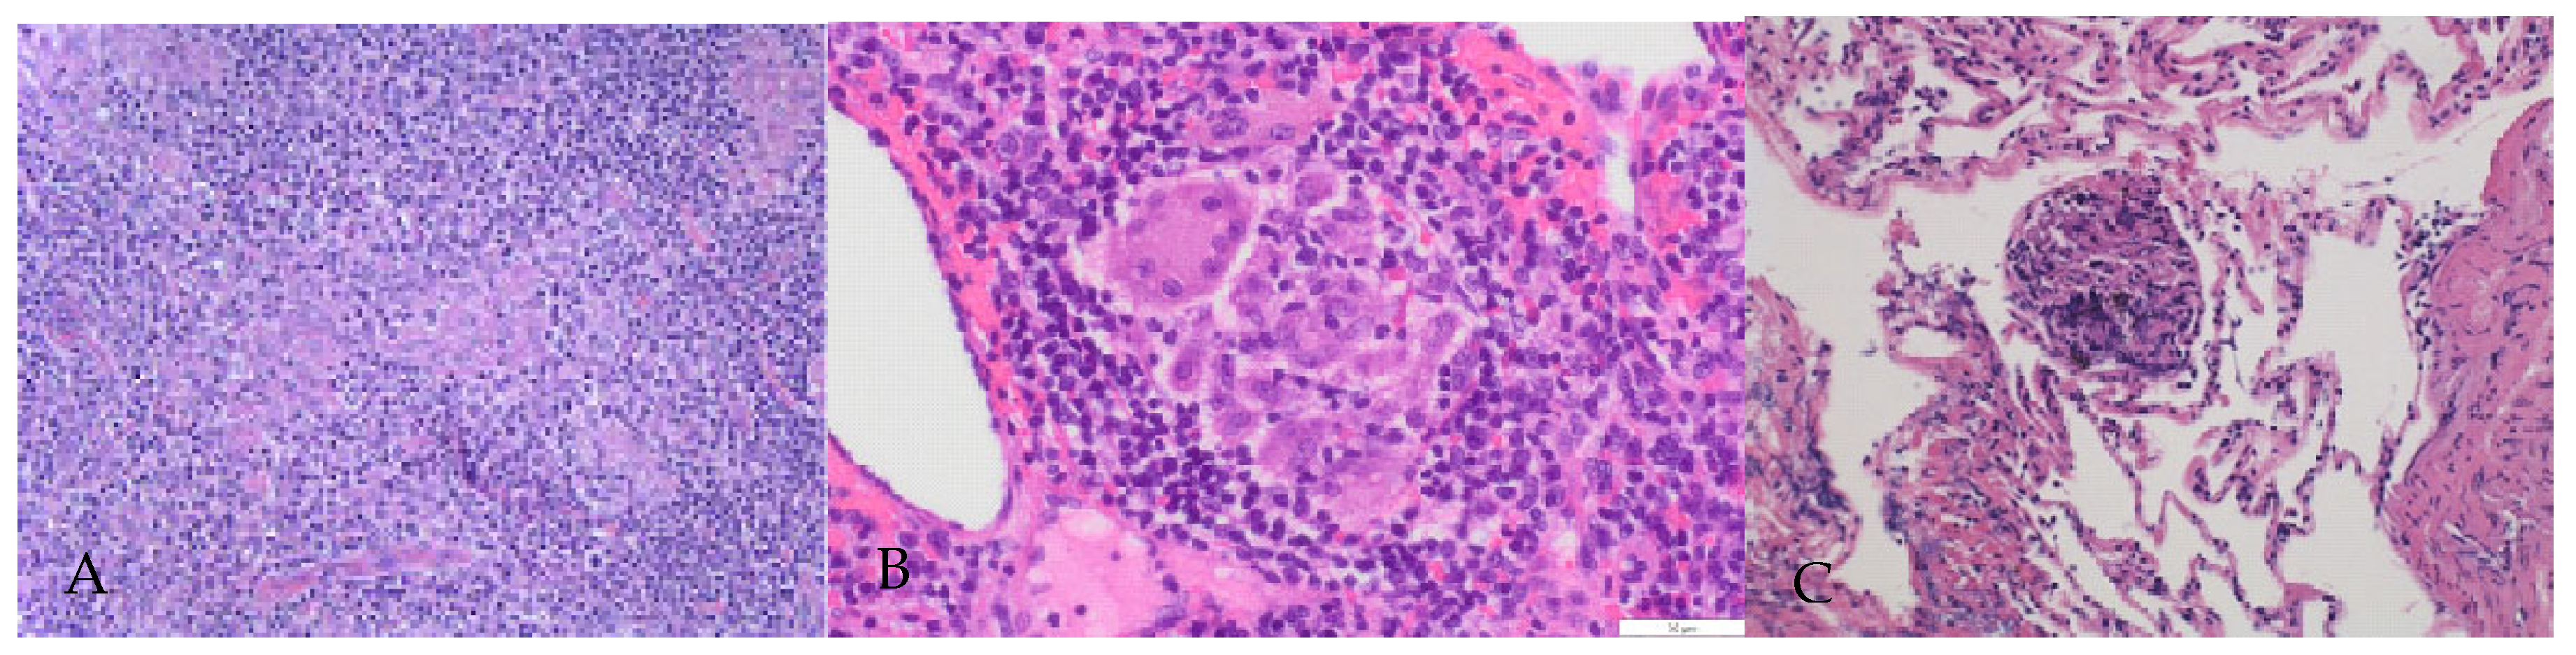

2. Case Presentation Section